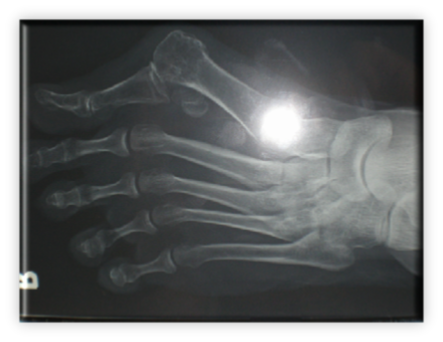

Πρόκειται για σύνθετη παθολογία του μεγάλου δακτύλου του ποδιού, που εκτός από την παραμόρφωση σε βλαισσότητα, όπως το όνομα υποδηλώνει, συνυπάρχει στροφική παραμόρφωση και γενικότερα παραμόρφωση ολόκληρου του πρώτου στοίχου (ταρσός, μετατάρσιο, δάκτυλο) αλλά και των μικρότερων δακτύλων. Πιο συγκεκριμένα, υπάρχουν οστεόφυτα στις αρθρώσεις και κυρίως στην έσω επιφάνεια της κεφαλής του πρώτου μεταταρσίου (κότσι), τροφικές αλλοιώσεις του δέρματος και δερματικοί κάλοι στα σημεία αυξημένης φόρτισης, λέπτυνση του υποδορίου λίπους στην πελματιαία επιφάνεια, εξάρθρημα σησαμοειδών οσταρίων, ανισορροπία στους άξονες έλξης των τενόντων περί του μεγάλου δακτύλου, υμενίτιδα στην έσω επιφάνεια της μεταταρσιοφαλλαγγικής η οποία είναι και πολύ επίπονη. Εμβιομηχανικά ο άξονας φόρτισης του ποδιού μεταφέρεται στο διάστημα μεταξύ πρώτου και δεύτερου στοίχου με αποτέλεσμα το πρώτο μετατάρσιο να δέχεται λιγότερα φορτία από όσο θα έπρεπε και τελικώς μεταταρσιαλγία στις κεφαλές των μικρότερων μεταταρσίων, παραμορφώσεις των μικρότερων δακτύλων με συχνότερη αυτή του δευτέρου που καταλήγει σε γαμψοδακτυλία, εφίππευση επί του πρώτου, στεόφυτα και δερματικό κάλο στην ραχιαία επιφάνεια της πρώτης φαλαγγοφαλαγγικής άρθρωσης, οστεοχόνδρινες αλλοιώσεις των αρθρώσεων και τελικά αρθρίτιδα.

ΒΛΑΙΣΟΣ ΜΕΓΑΛΟΣ ΔΑΚΤΥΛΟΣ (HALLUX VALGUS)

Στις ακτινογραφίες πρέπει να μετρηθούν η γωνία μεταξύ 1ου και 2ου μεταταρσίων με ανώτερα όρια 8-9 μοίρες, η γωνία βλαισσότητας του 1ου μεταταρσίου και 1ης φάλαγγας που όταν ξεπερνά τις 15 μοίρες ορίζεται παθολογική. Συμπληρωματικά μπορούν να μετρηθούν οι γωνίες προσανατολισμού της αρθρικής επιφάνειας κεφαλής 1ου μεταταρσίου και η γωνία προσανατολισμού κεντρικής αρθρικής επιφάνειας 1ης φάλαγγας του μεγάλου δακτύλου.